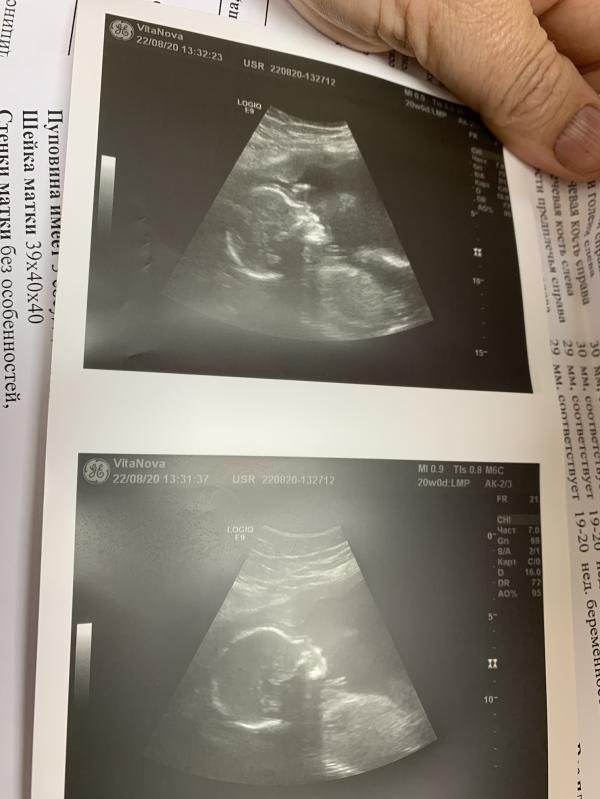

Вот он мой носатый сынок! Меня так распирает посмотреть на него и узнать на кого же он похож! Какая странная штука гены! Мои двойняшки такие разные, одна копия меня , вторая в мужа породу, но глаза и волосы светлые, хотя они все темные! Тут даже не представляю на кого он похож, но очень бы хотелось чтоб на меня! А ваши детки на кого похожи???